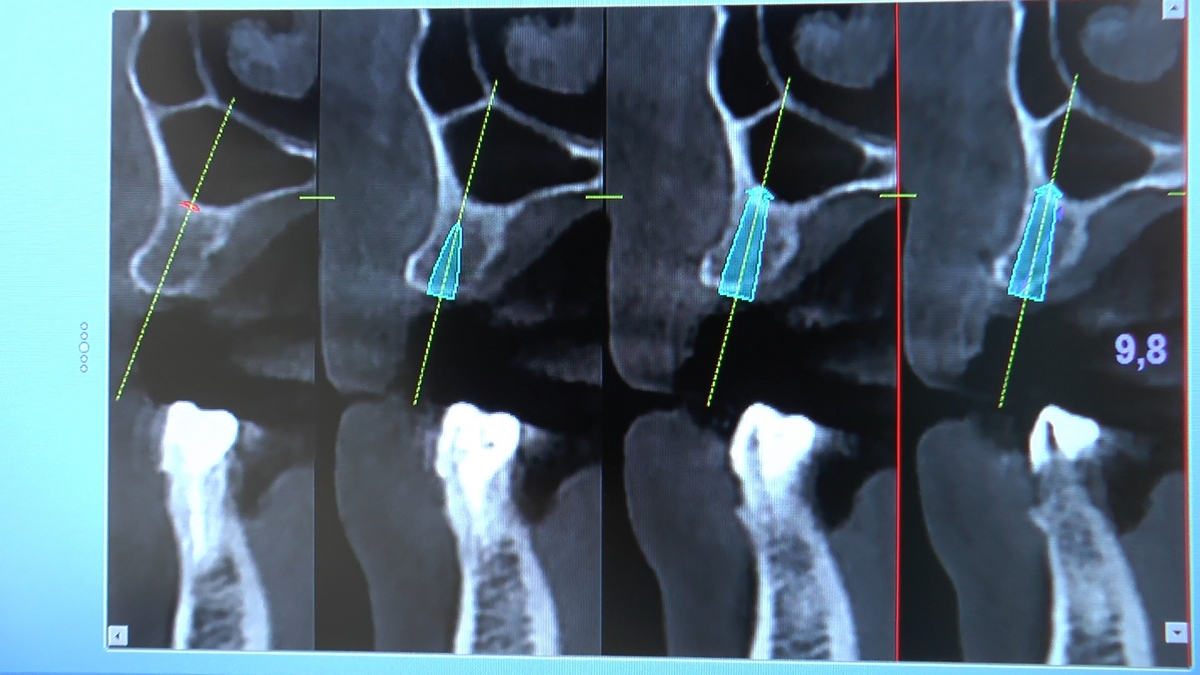

Wprowadziliśmy łącznie 25 implantów w tym wykonaliśmy:

dwa zabiegi All- on -4 / jeden w szczęce, jeden w żuchwie/ z usunięciem zębów i natychmiastową implantacją oraz natychmiastową odbudową protetyczną

jeden zabieg sinus lift otwarty